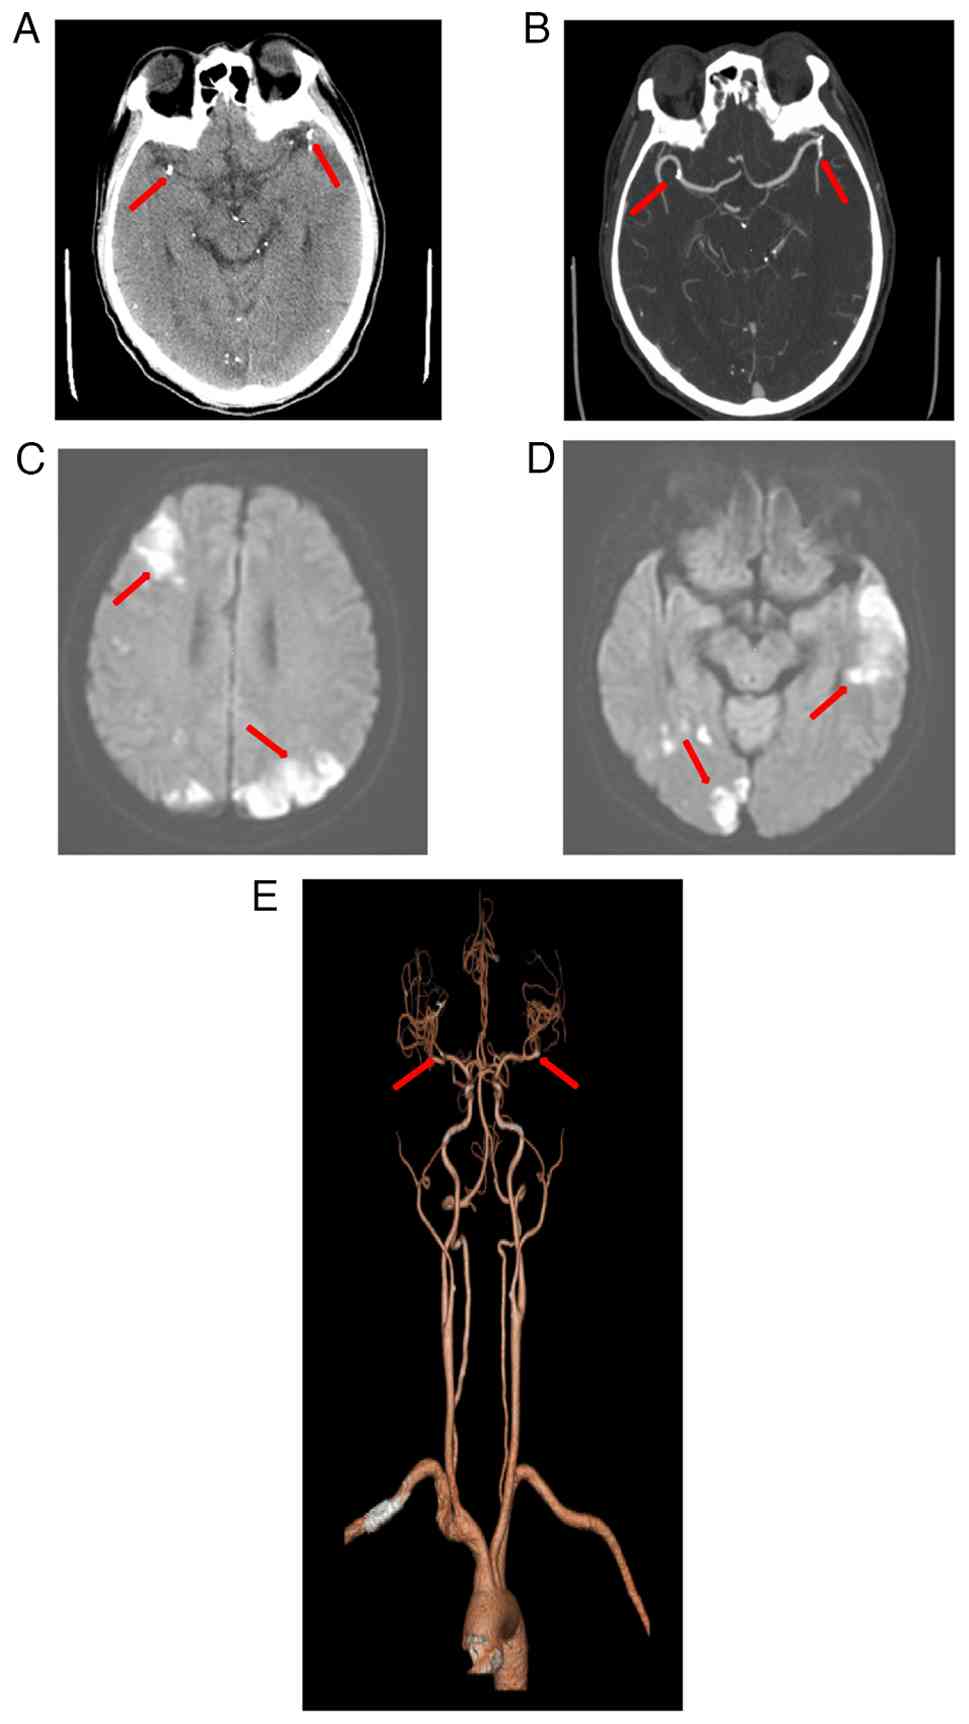

Embolization of the varices was performed through a 4F Cobra catheter by slow injection of a 1:1 mixture of 2 ml tissue adhesive (GLUBRAN2) and 2 ml iodized oil under fluoroscopic control. Pre- and post-TIPS portal pressure gradients were 32 and 17 mmHg, respectively, indicating successful decompression. At ~24 h post-surgery, the patient developed sudden bilateral vision loss and lower limb weakness (grade III muscle strength bilaterally). Magnetic resonance angiography showed embolic occlusion of branches of the middle cerebral artery. Emergent neuroimaging including non-contrast CT and diffusion-weighted MRI revealed multiple acute infarctions in the bilateral frontal lobe, parietal lobe, occipital lobe, temporal lobe, left thalamus and cerebellar hemisphere (Fig. 1A-E).

Multimodal imaging evaluation

revealing acute cerebral infarction. (A) Axial head CTA

demonstrates spotty and nodular high-density filling of the

sclerosing agent within the distal M1 segments of the bilateral

MCAs. (B) Head CTA maximum intensity projection reveals cast-like

high-density filling in the distal M1 segments of the bilateral

MCAs. (C) Brain MRI (DWI, b=800) shows multiple patchy hyperintense

lesions in the right frontal lobe and bilateral parietal lobes. (D)

Brain MRI DWI (b=800) displays multiple patchy hyperintense lesions

in the right temporo-occipital region and the left temporal lobe.

(E) Head CTA volume rendering depicts the abrupt cutoff of the

distal M1 segments of the bilateral MCAs, accompanied by sparse and

reduced distal branching. CTA, CT angiography; MCA, middle cerebral

artery; DWI, diffusion-weighted imaging. (A, B and E) Arrows refer

to the positions filled with sclerosing agents in the cerebral

arteries. (C and D) Arrows refer to the part of the cerebral

infarction caused by arterial blockage.

Figure 1

Multimodal imaging evaluation revealing acute cerebral infarction. (A) Axial head CTA demonstrates spotty and nodular high-density filling of the sclerosing agent within the distal M1 segments of the bilateral MCAs. (B) Head CTA maximum intensity projection reveals cast-like high-density filling in the distal M1 segments of the bilateral MCAs. (C) Brain MRI (DWI, b=800) shows multiple patchy hyperintense lesions in the right frontal lobe and bilateral parietal lobes. (D) Brain MRI DWI (b=800) displays multiple patchy hyperintense lesions in the right temporo-occipital region and the left temporal lobe. (E) Head CTA volume rendering depicts the abrupt cutoff of the distal M1 segments of the bilateral MCAs, accompanied by sparse and reduced distal branching. CTA, CT angiography; MCA, middle cerebral artery; DWI, diffusion-weighted imaging. (A, B and E) Arrows refer to the positions filled with sclerosing agents in the cerebral arteries. (C and D) Arrows refer to the part of the cerebral infarction caused by arterial blockage.